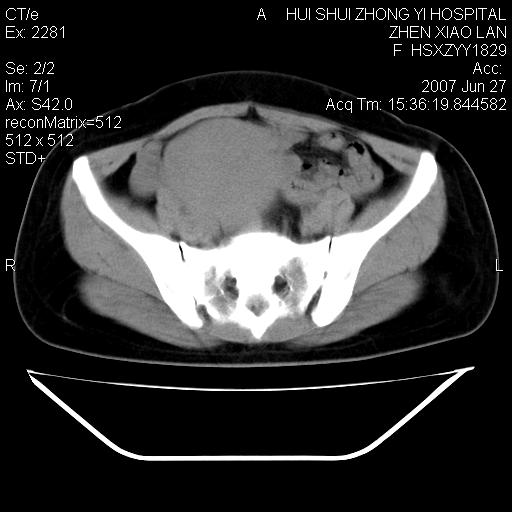

以下是引用还珠格格在2007-6-28 15:15:00的发言:[br]子宫明显增大,偏向盆腔右侧,密度均匀,和子宫同密度, 考虑 子宫肌瘤可能性大 建议增强 除外子宫平滑肌肉瘤。

以下是引用dyqct在2007-6-28 15:41:00的发言:[br]考虑多发子宫肌瘤可能性大,建议进一步增强检查。